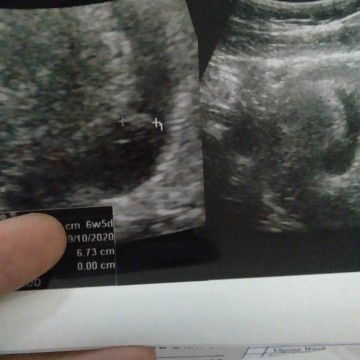

detak jantung blm ada

Hay momm... Usia kandunganku 7minggu tp dokter bilang janinku blm ada detak jantungnya dokter bilanv seharusnya usia kandungan 7minggu sudah terdengar... Dan dokter pun memberi resep obat untuk janinku dan kembali kontrol lgi setelah dua minggu Apa mommy moomy disini sudah pernah ada yg merasakan sepertiku